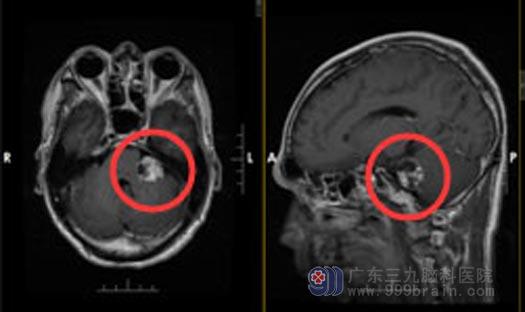

手术前

手术中,发现肿瘤位于左侧桥小脑角,黄白色,质中,显微镜下电凝分块切除,肿瘤卒中,听神经、面神经位于肿瘤前下方,经分离面神经保留完整,三叉神经、舌咽神经受肿瘤压迫明显,细心分离完整保留,脑干表面肿瘤粘连紧密,肿瘤基底部位于内听道,予反复电凝烧灼,术腔止血彻底,硬膜补片严密缝合硬膜,手术经过顺利.